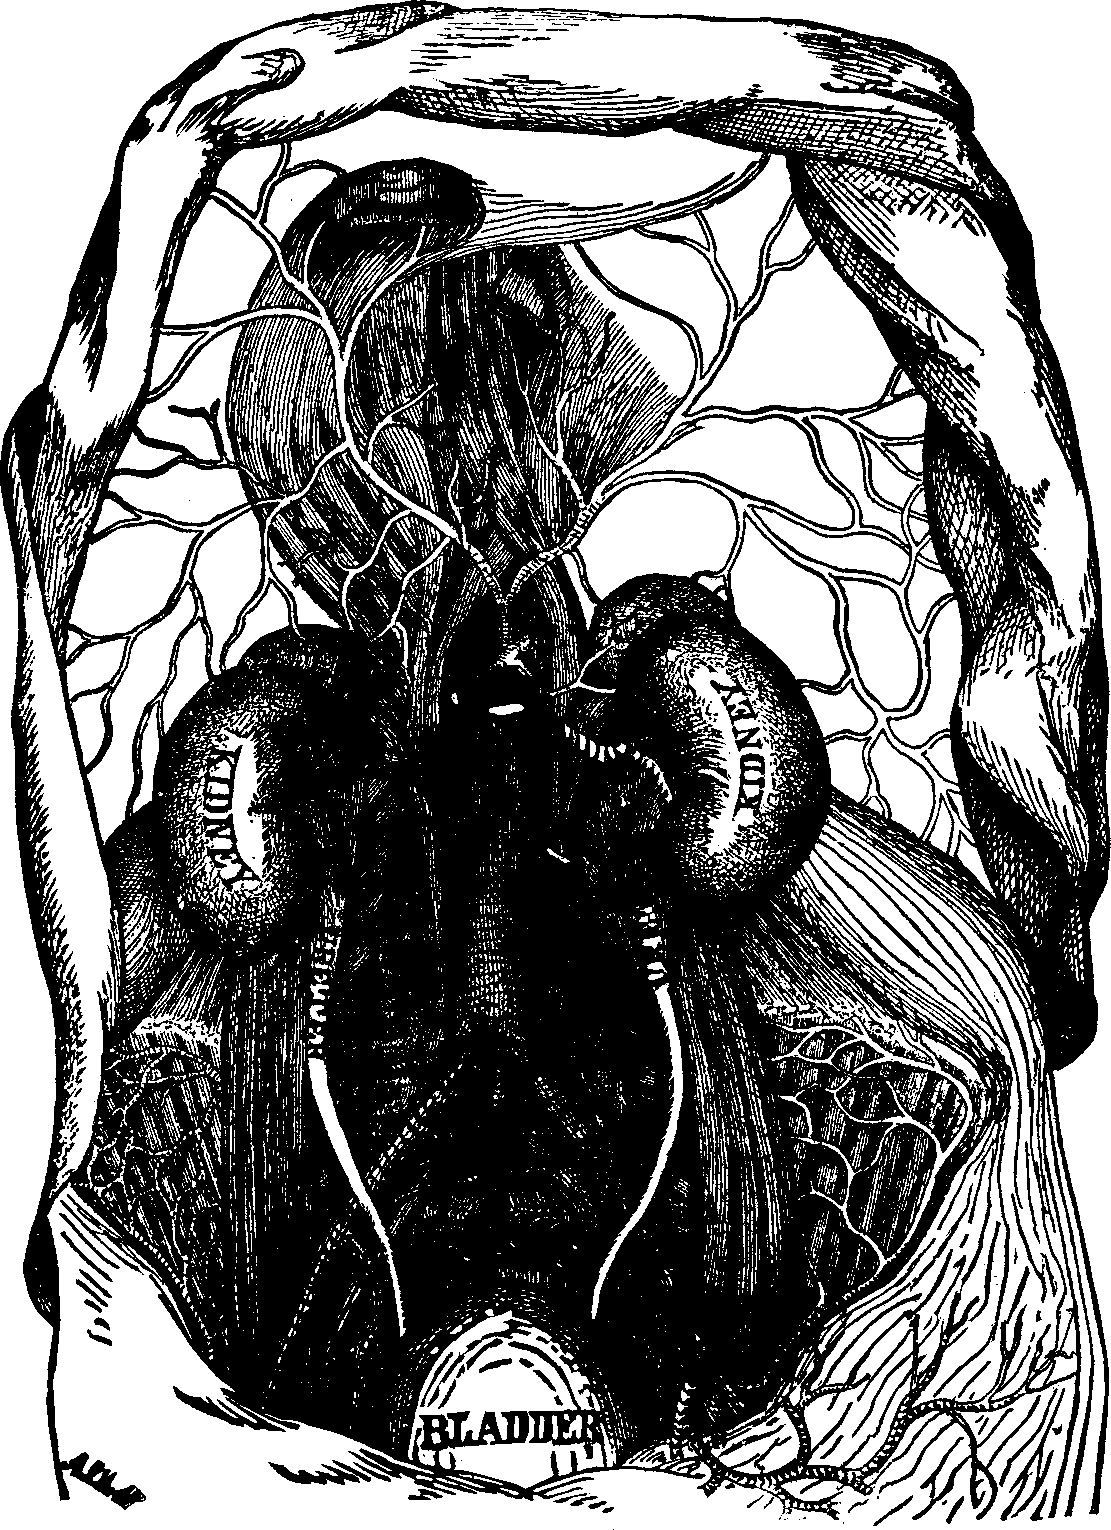

Fig. 33. The inferior surface of the liver. 1. Right lobe. 2.

Left lobe. 3. Gall-bladder.

The Liver, which is the largest gland in the body, weighs [pg 43]about four

pounds in the adult, and is located chiefly on the right side, immediately

below the diaphragm. It is a single organ, of a dark red color, its upper

surface being convex, while the lower is concave. It has two large lobes,

the right being nearly four times as large as the left. The liver has two

coats, the serous, which is a complete investment, with the

exception of the diaphragmatic border, and the depression for the

gall-bladder, and which helps to suspend and retain the organ in position;

and the fibrous, which is the inner coat of the liver, and forms

sheaths for the blood-vessels and excretory ducts. The liver is abundantly

supplied with arteries, veins, nerves, and lymphatics. Unlike the other

glands of the human body, it receives two kinds of blood; the arterial for

its nourishment, and the venous, from which it secretes the bile. In the

lower surface of the liver is lodged the gall-bladder, a membranous sac, or

reservoir, for the bile. This fluid is not absolutely necessary to the

digestion of food, since this process is effected by other secretions, nor

does bile exert any special action upon, starchy or oleaginous substances,

when mixed with them at a temperature of 100° F. Experiments also show

that in some animals there is a constant flow of bile, even when no food

has been taken, and there is consequently no digestion to be performed.

Since the bile is formed from the venous blood, and taken from the waste

and disintegration of animal tissue, it would appear that it is chiefly an

excrementitious fluid. It does not seem to have accomplished its function

when discharged from the liver and poured into the intestine, for there it

undergoes various alterations previous to re-absorption, produced by its

contact with the intestinal juices. Thus the bile, after being [pg

44]transformed in the intestines, re-enters the blood under a new

form, and is carried to some other part of the system to perform its

mission.